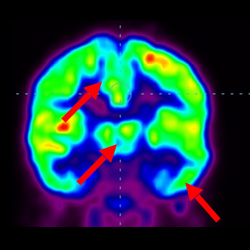

腦癱細胞療法, 腦癱治療

細胞治療前 PET CT 掃描顯示神經(jīng)組織中的藍/黑色區域,表明腦癱引起的大腦損傷。

細胞治療后,藍色和黑色區域減少,并且看到更活躍的區域。這表明損傷減少并改善了大腦功能。